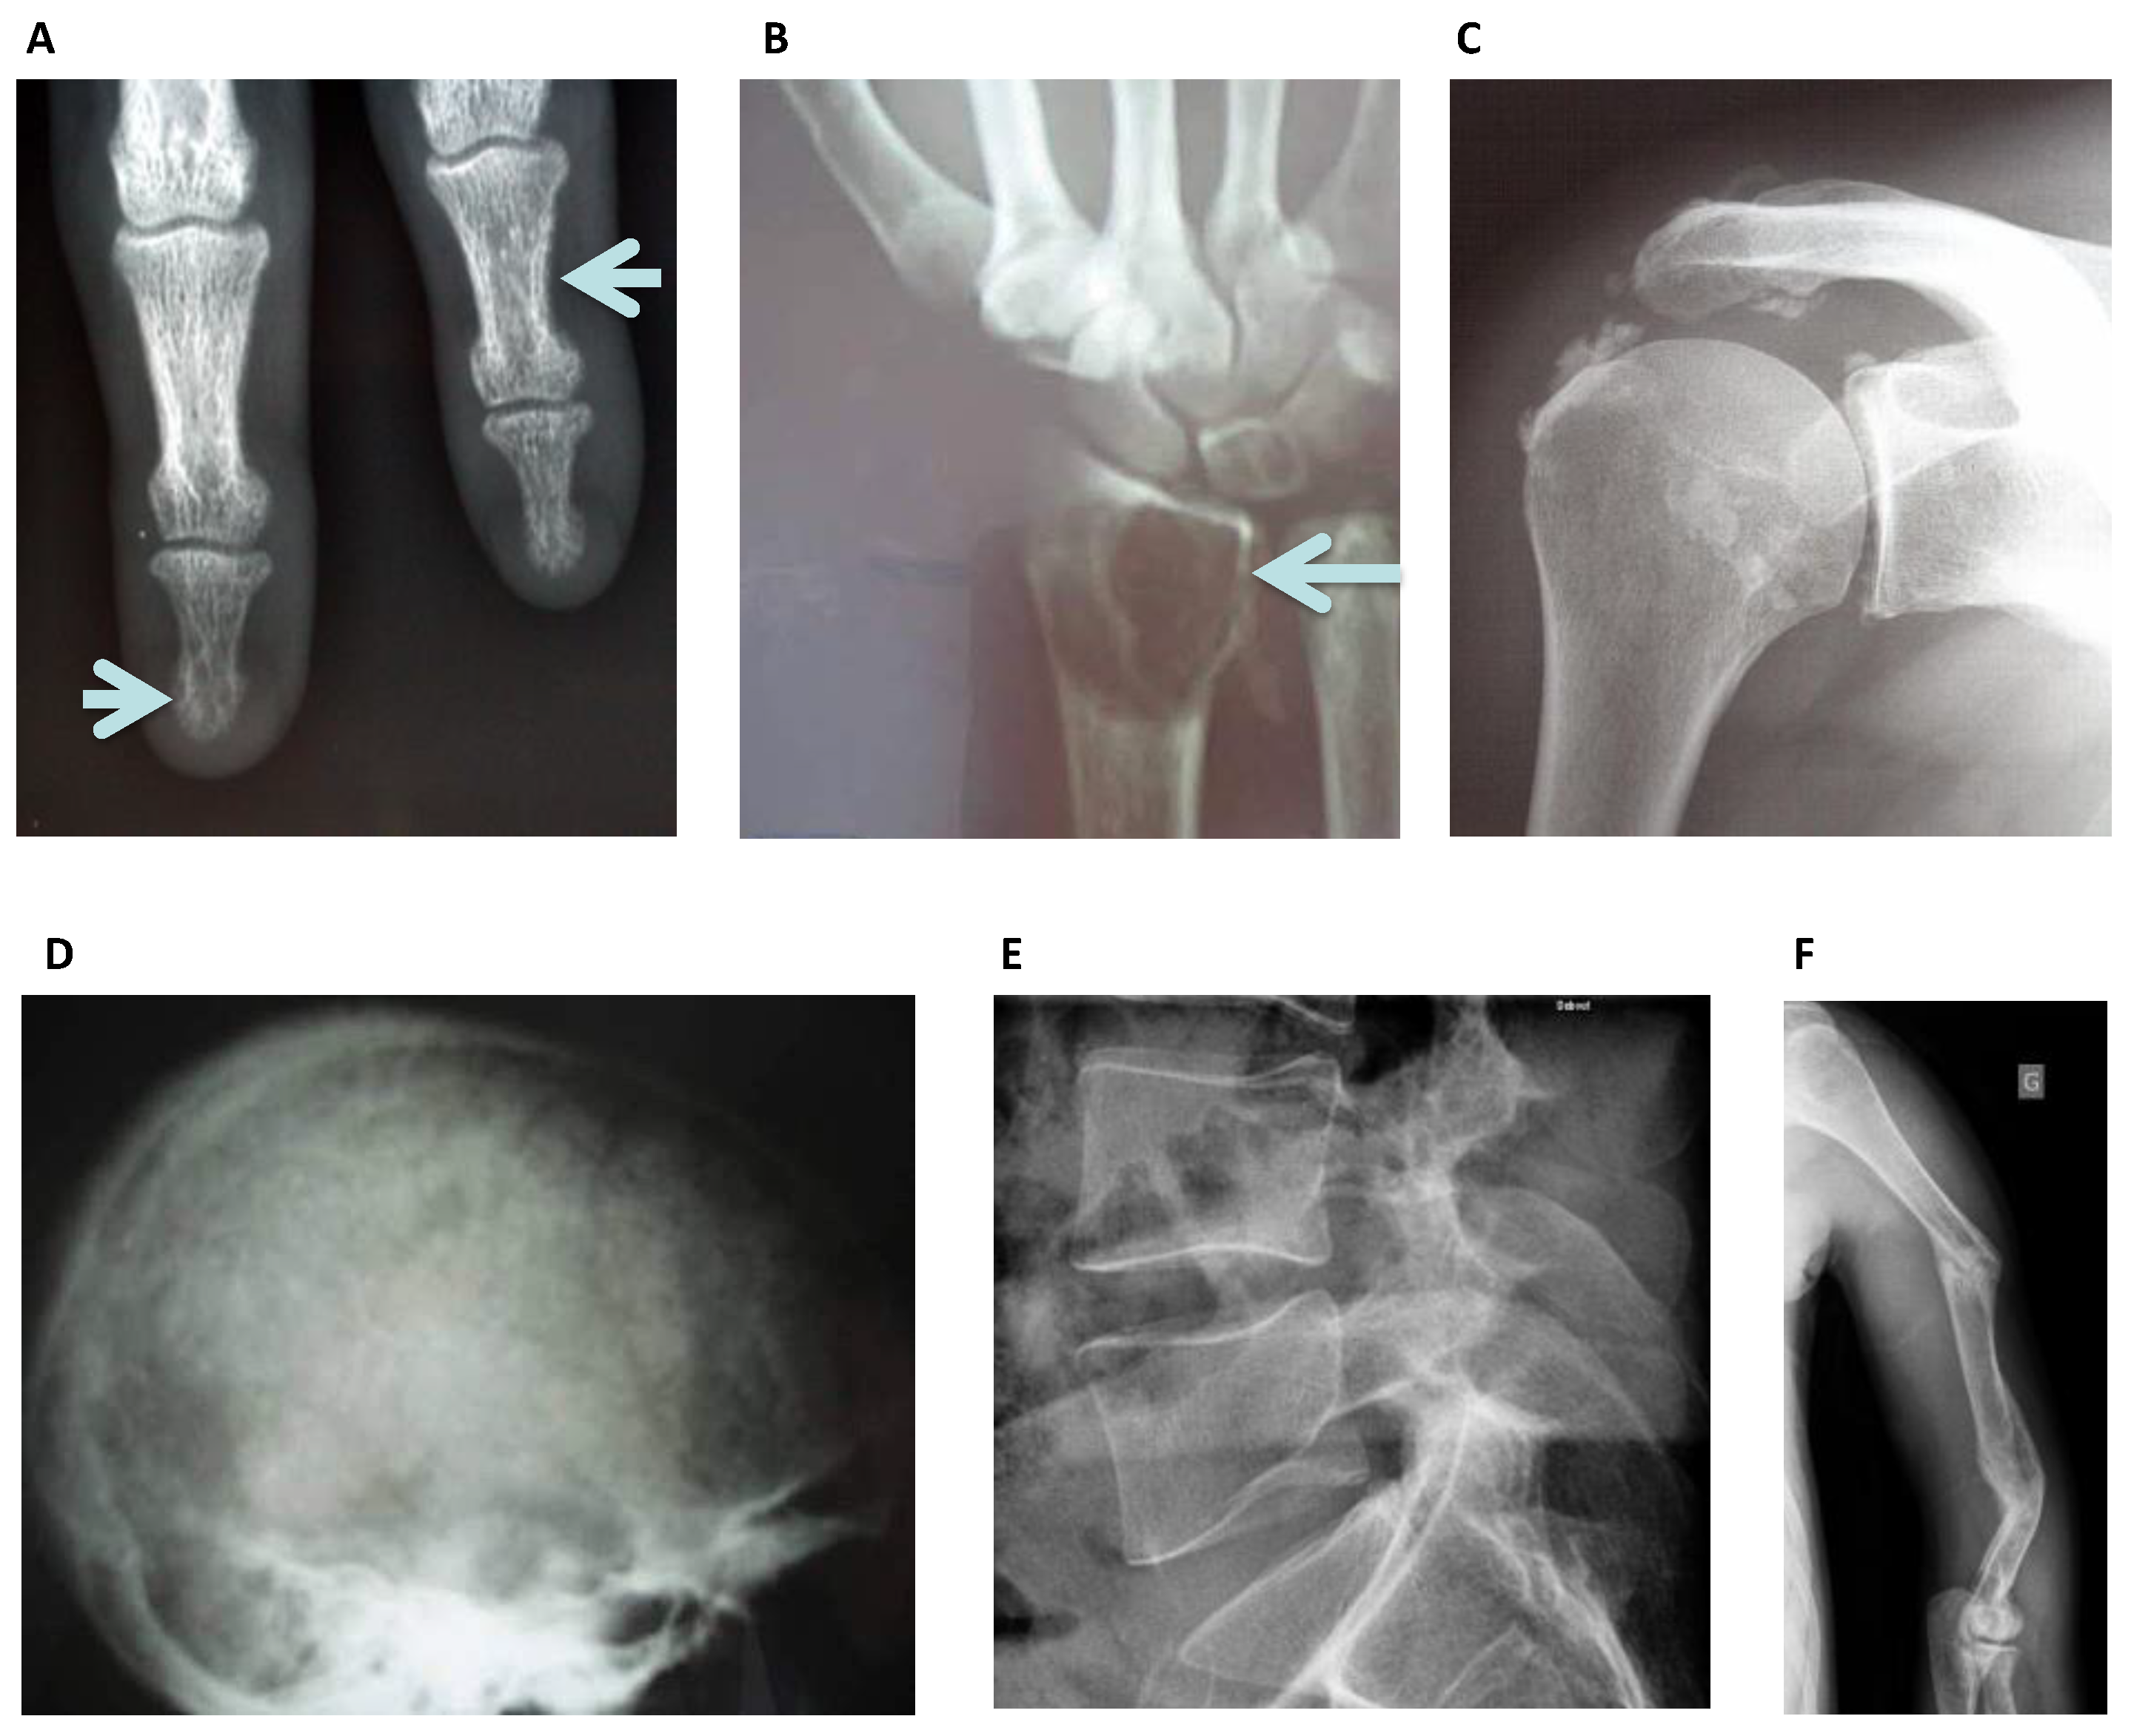

3.1. Conventional Radiography

- Lim, C.Y.; Ong, K.O. Various musculoskeletal manifestations of chronic renal insufficiency. Clin. Radiol. 2013, 68, e397–e411. [Google Scholar] [CrossRef] [PubMed]

- Alexander, A.J.; Jahangir, D.; Lazarus, M.; Sprague, S.M. Imaging in Chronic Kidney Disease-Metabolic Bone Disease. Semin. Dial. 2017, 30, 361–368. [Google Scholar] [CrossRef]

- Jevtic, V. Imaging of renal osteodystrophy. Eur. J. Radiol. 2003, 46, 85–95. [Google Scholar] [CrossRef]

- Murphey, M.D.; Sartoris, D.J.; Quale, J.L.; Pathria, M.N.; Martin, N.L. Musculoskeletal manifestations of chronic renal insufficiency. Radiographics 1993, 13, 357–379. [Google Scholar] [CrossRef]

| Plain Radiography | Bone resorption lesions Bone cysts Fractures | Sub-periosteal Subchondral Sub-tendinous Extra-skeletal calcifications All skeleton | Secondary Hyperparathyroidism Multiple Myeloma Amyloidosis Osteonecrosis Osteoporosis Calcific Uremic Arteriolopathy | All |